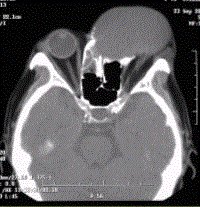

问题 患者男,60岁,头痛,前额部局部隆起。查体:前额隆起处可触及乒乓球样肿块,CT显示如下图。 鼻窦黏液囊肿的发病机制为

选项 A.窦壁黏膜下腺体轻度炎症或变态反应 B.乳牙根管感染 C.龋齿使牙髓慢性感染坏死 D.鼻窦的自然开口长期阻塞 E.发病机制不清楚 F.窦腔开口变异

答案 D